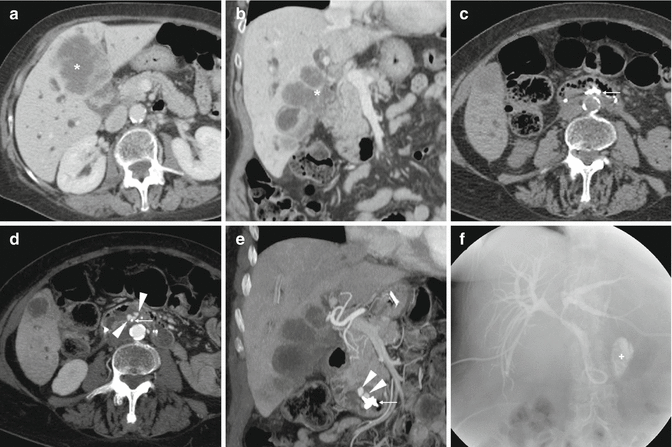

Photo Credit by: bing.com / after ercp stool findings endoscopic complications imaging retrograde

Photo Credit by: bing.com / ercp after stool findings imaging retrograde endoscopic complications

Photo Credit by: bing.com / after ercp stool complications imaging endoscopic findings retrograde